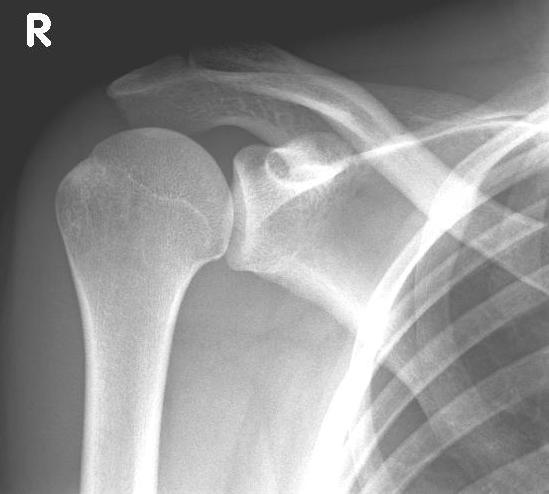

In most cases, the reason for the installation of a shoulder prosthesis is painful joint wear ("omarthrosis"), which is usually associated with a significant restriction of shoulder function.

Several factors can be responsible for the pronounced cartilage or bone wear between the humeral head and glenoid cavity.

In most cases, the wear and tear or destruction of the shoulder joint results from age-related and/or increased mechanical stress.

In addition, consequences of accidents (e.g. a fracture of the humeral head), older tendon tears (rotator cuff defects), circulatory disorders of the humeral head, chronic rheumatoid arthritis or premature wear due to chronic joint instability can be responsible for the development of omarthrosis.

left: X-ray image of an omarthrosis

right: X-ray of a healthy shoulder joint

X-rays can be used to reliably diagnose the extent of joint wear. In the case of severe osteoarthritis, for example, the joint space and the formation of jagged edges (osteophytes) can be detected. If additional damage to the tendons of the shoulder (rotator cuff) is suspected, ultrasound examination (sonography) or magnetic resonance imaging (MRI) can help clarify the situation.